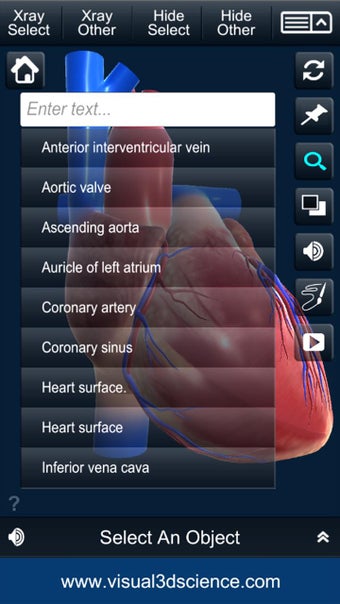

El usuario puede seleccionar cualquier parte del corazón para ver su nombre o leer información relacionada.

Puedes seleccionar la vista de rayos X, ocultar y mostrar partes del corazón, así como ver animaciones en tiempo real, dibujar o escribir en la pantalla y compartir capturas de pantalla, pronunciación de audio para todos los términos de anatomía y más.